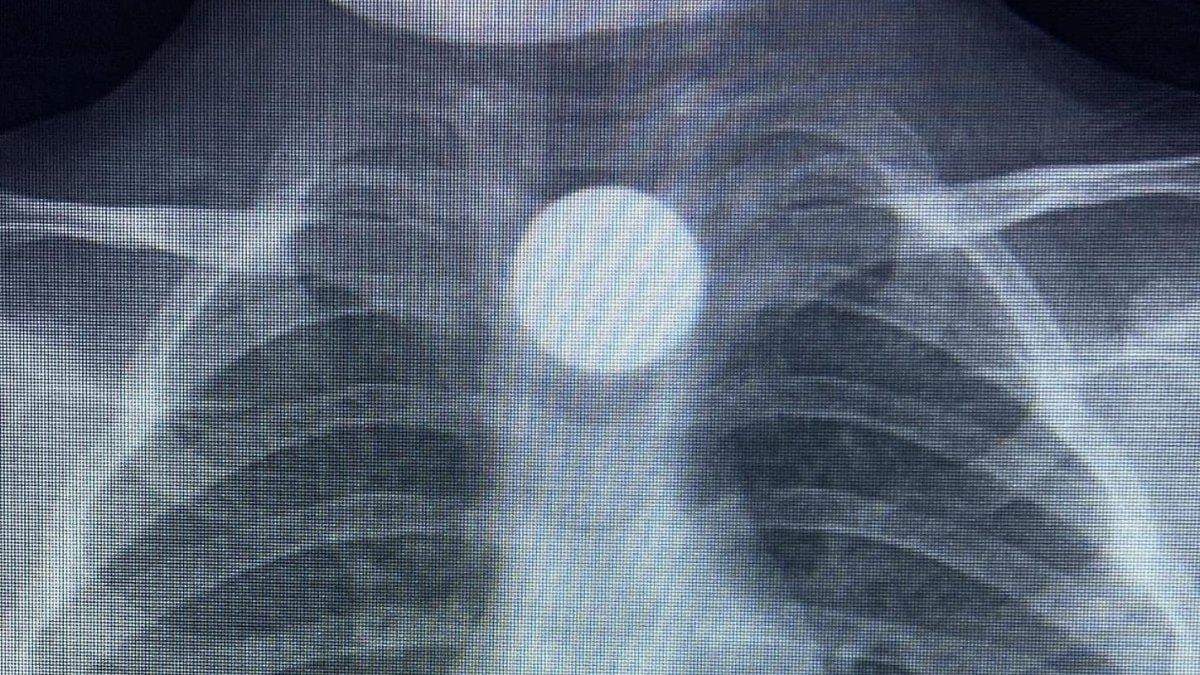

Çocuğun parayı yuttuğunu fark eden ailesi, Bilal K.’yi vakit kaybetmeden özel araçla İnegöl Devlet Hastanesi’ne götürdü. Hastanede yapılan muayene ve görüntüleme işlemlerinde, madeni paranın çocuğun yemek borusunda takılı kaldığı tespit edildi.